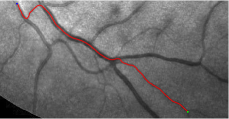

Compare to existing minimal path models. The Riemannian metrics used in [1, 4, 5] are based on the local pointwise information. The curvature-penalized metric [7, 6] and the proposed coherence-penalized metric are able to consider more constraints, i.e., the rigidity for [7, 6] and feature coherence for our metric. These constraints are beneficial to the respective geodesics to reduce the risk of short branches combination problem. Compared to the curvature-penalized metric, our method can be more flexible since the feature map can be produced dependently on the task. In retinal imaging, veins and arteries are distinguishable in terms of gray levels or vesselness values, satisfying the formulation of the proposed model. Especially for vessels with strong tortuosity, the curvature-penalized metric, which favours a smooth curve, fails to catch the expected vessels as shown in the left column of Fig. 2. From the right column of Fig. 2, one can see that our model can obtain a good result.

Validation. We validate our minimal path model on respective 54 and 30 patches obtained from the DRIVE [14, 15] and the IOSTAR [16] datasets with AV groundtruth. Each artery involved in these parches locates near a vein or crossing it at least once. Our goal is to extract the artery between two given points. In order to get the quantitative evaluation, we first convert each continuous spatial path to an 4-connected digital path which is considered as a pixel collection. We denote by the collection of digital path pixels inside the artery groundtruth map . Thus, a measure can be simply defined as , where and mean the respective number of elements involved in and . We compare our model to four existing minimal path models: the isotropic Riemannian (IR) model [1], the anisotropic radius-lifted Riemannian (ArR) model [4], the isotropic orientation-lifted Riemannian (IoR) model [5] and the curvature-penalized (CuP) model [7]. The construction of these metrics are based on the OOF outputs [12]. Note that a centerline-based potential is chosen so that we remove the radius dimension of [5] to reduce computation complexity. The results in terms of the score are presented in Table 1, including the average (Avg.), maximum (Max.), minimum (Min.) and standard deviation (Std.) values. In both DRIVE and IOSTAR datasets, our method can achieve the best performances thanks to the coherence penalization. Note that in Table 1, we evaluate our method by using the refined paths instead of using the original coherence-penalized minimal paths. For comparisons in visualization, we show the minimal paths from the ArR metric , the CuP metric and the proposed coherence-penalized metric on three retinal patches as shown in Fig. 3. The targeted artery vessels which cross veins at least once are labeled by red color in column 1. The paths shown in column 4 from the proposed metric are results after refinement. One can claim that our method indeed can catch expected arteries while other metrics fall into the traps of short branches combination.